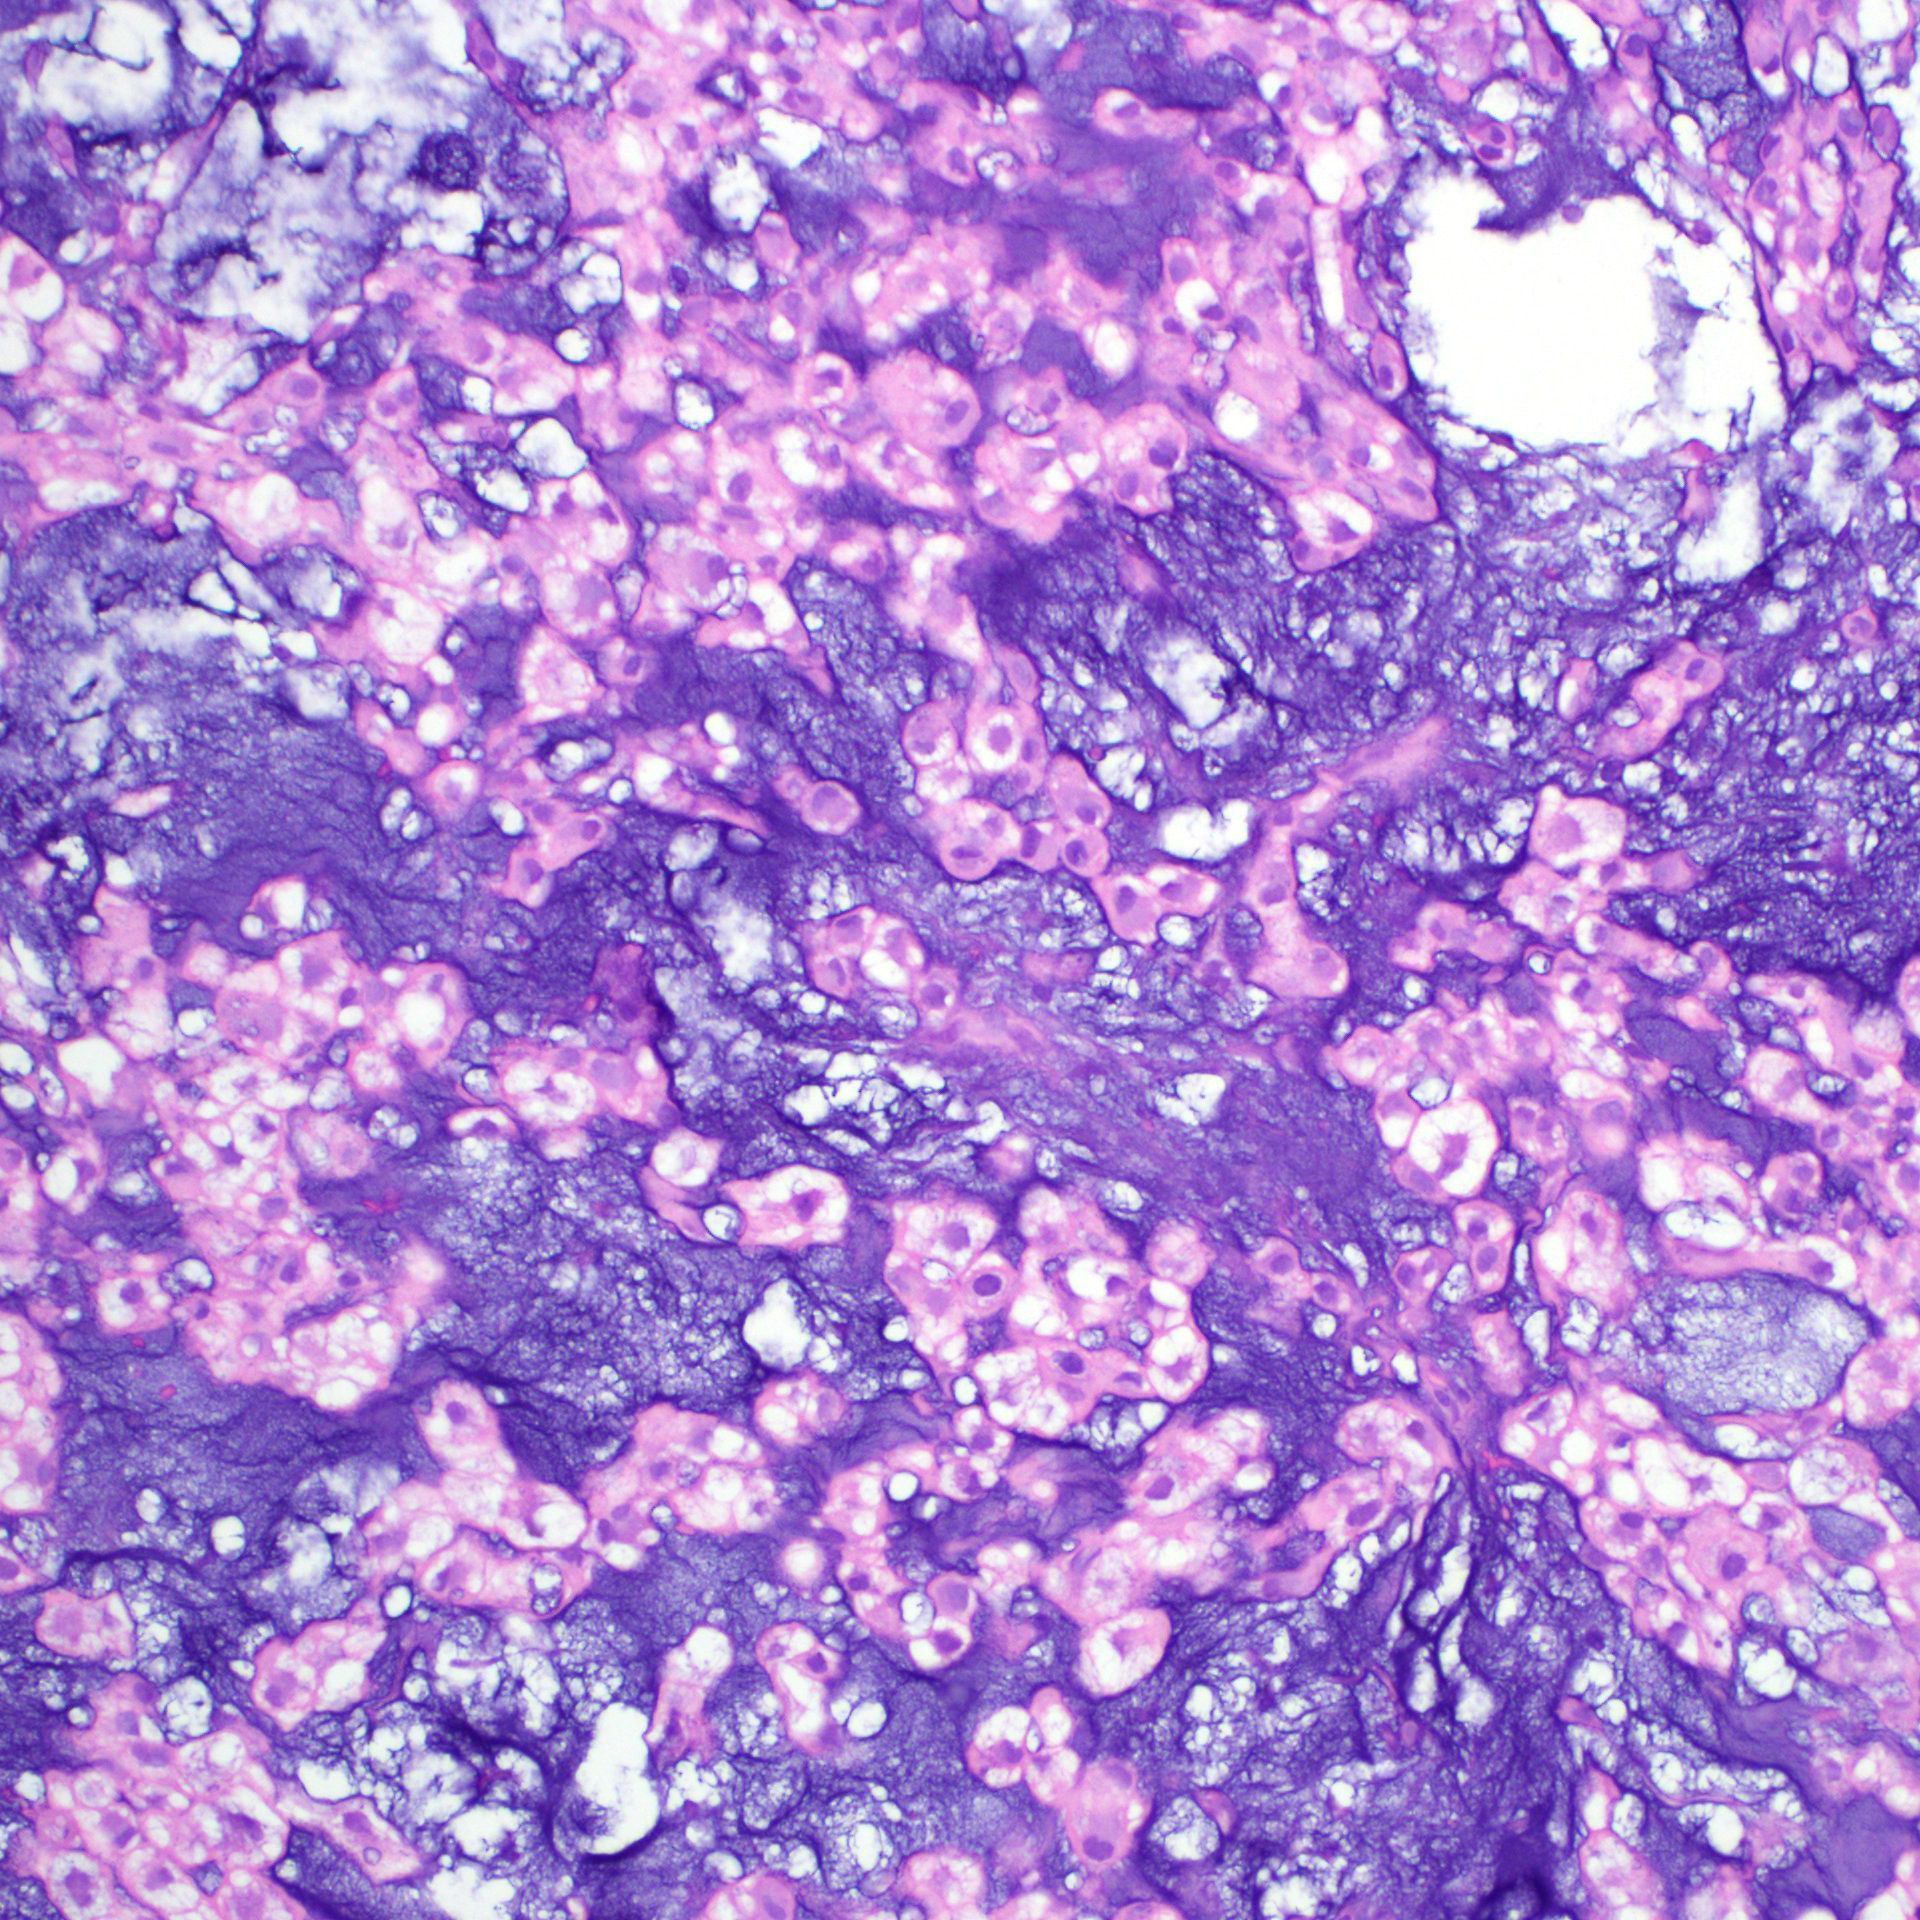

What process is happening here? How old is this patient?